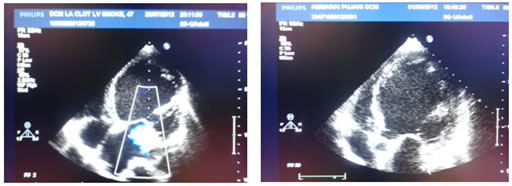

In present study, left ventricular dimensions were less but all patients had global hypokinesia and poor ejection fraction. LVPW and IVS thickness was within normal limits. Right ventricular dilatation was seen in 20 (40%) of patients and mean right ventricular diameter was 22.84 ± 7.20 mm. Left atrial enlargement was seen in 27 (54%) patients and mean LA diameter was 40.94 ± 6.30 mm. Valvular regurgitation was seen in 43 (86%) of patients. There was isolated MR in 12 (24%) of patients, while MR was associated with TR in 26 (52%) patients and with TR and AR in 4 (8%) patients. There was isolated TR in 1 (2%) patient. Diastolic dysfunction was present in 21 (42%) patients in the present study. Pericardial effusion was present in 15 (30%) patients. In 5 (10%) patients, clots were detected (Table 4 and 5) (Fig. 1 and 2).

Fig 1 and 2: Echocardiographic features of dilated cardiomyopathy